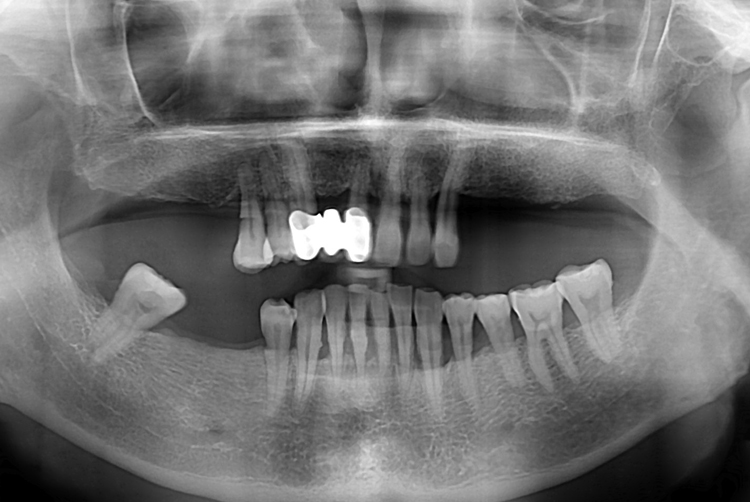

[임플란트] 어금니 임플란트

치료전 : 2018-12-14